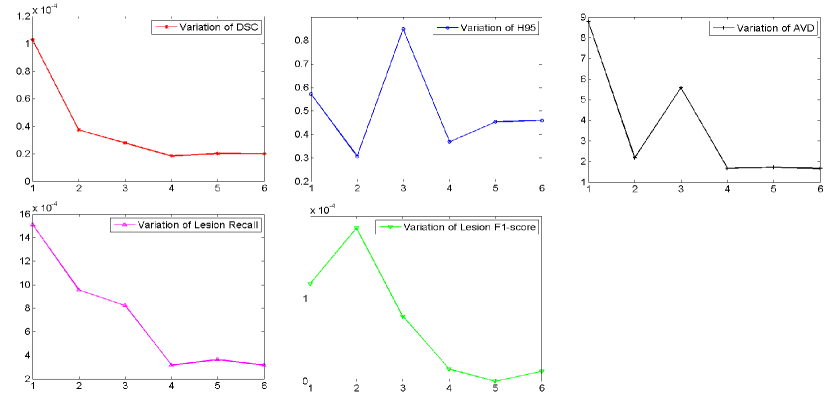

5.6 Effect of the size of ensembles

Ensemble learning aims at aggregating different models to boost the segmentation performance. The optimal size of an ensemble, i.e., how many models in the ensemble are needed, still remains an open issue and, as in many related ensemble learning task, a task specific parameter that needs to be optimized. To this end, we evaluated how the segmentation performance behaves over the number of ensemble models. We split the public dataset into training set and validation set by randomly picking 80% and 20% cases from each scanner respectively. The models were trained on 48 cases and validated on 12 cases. Then the segmentation performance on 12 cases were averaged on each evaluation metric. For each model with different size of ensembles, the training process was repeated five times and the segmentation results on the validation set were averaged.

Figure 13 shows the curves of segmentation performance on five metrics w.r.t different ensemble size. It could be seen that (1) the ensemble with three or more models clearly outperformed the ensemble of only one model on all of the five metrics. The improvement of ensemble model with size over one with size is statistically significant on five metrics, all with small p-values; (2) when the size was further increased, performance tended to saturate and minor improvements in some of the measures came at the cost of small decreased in others. Figure 14 shows standard deviation of segmentation performance between five repeated trained models w.r.t different ensemble size. It could be observed that the variation of segmentation performance was reduced on the main evaluation metrics when the size of ensemble was increased. It demonstrated that the ensemble model can not only boost the segmentation performance but also guarantee a robust segmentation result. Figure 15 shows a case segmented by three individual models and their ensemble. We observed that three models trained with different weights initializations and shuffled data generated significantly different result on boundary and small lesions. And the model ensemble avoided the worst segmentation result.